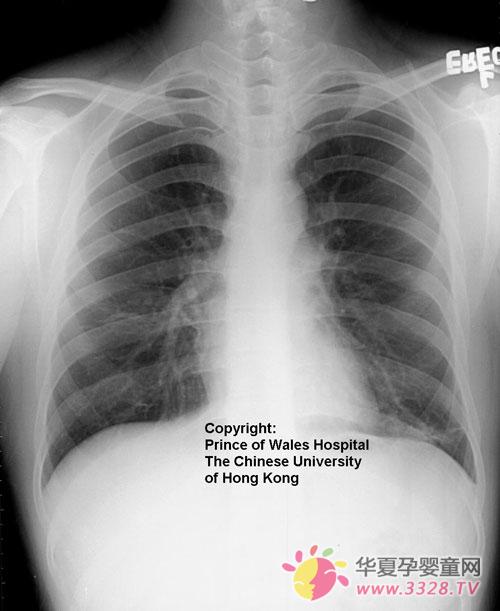

非典型肺炎该如何治疗